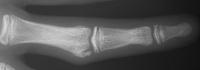

Case 3. 21 year old woman with pain developing in a congenitally angulated thumb.

Radiographs show a juxtaarticular ossification with  subchondral cyst formation of the bone interface with the lateral phalangeal head and lateral angulation of the proximal phalanx articular surface.